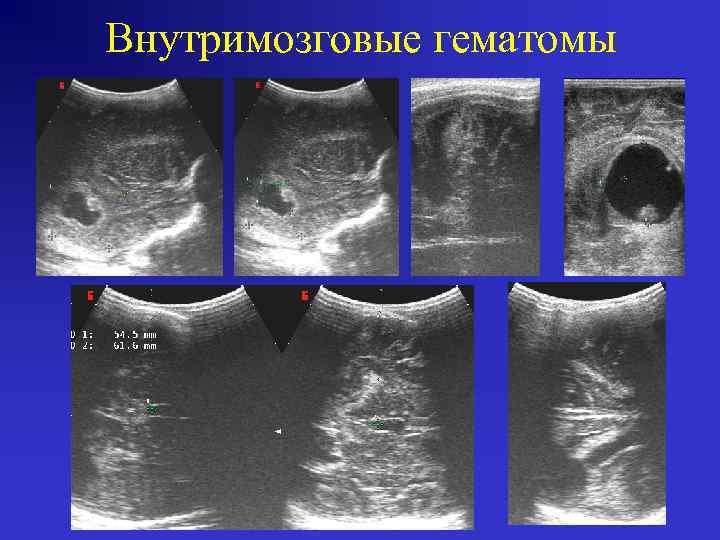

Первичная внутримозговая гематома (ВМГ). • Источник первичных ВМГ – повреждённый сосуд в области гематомы (следствие механической травмы, васкулита, аномалии ). • Гиперэхогенный очаг в паренхиме мозга с чётким полицикличным контуром. • При обширных поражениях может выявляться прорыв в боковые желудочки, вторичное субарахноидальное кровоизлияние. • «Масс-эффект» со сдавлением и смещением близрасположенных структур. • В резидуальном периоде (8 -10 недель) формируется внутримозговая (при изолированном кровоизлиянии) и порэнцефалическая (при прорыве в желудочки) кисты.

Первичная внутримозговая гематома (ВМГ).

Внутримозговые гематомы операция

Внутримозговые гематомы